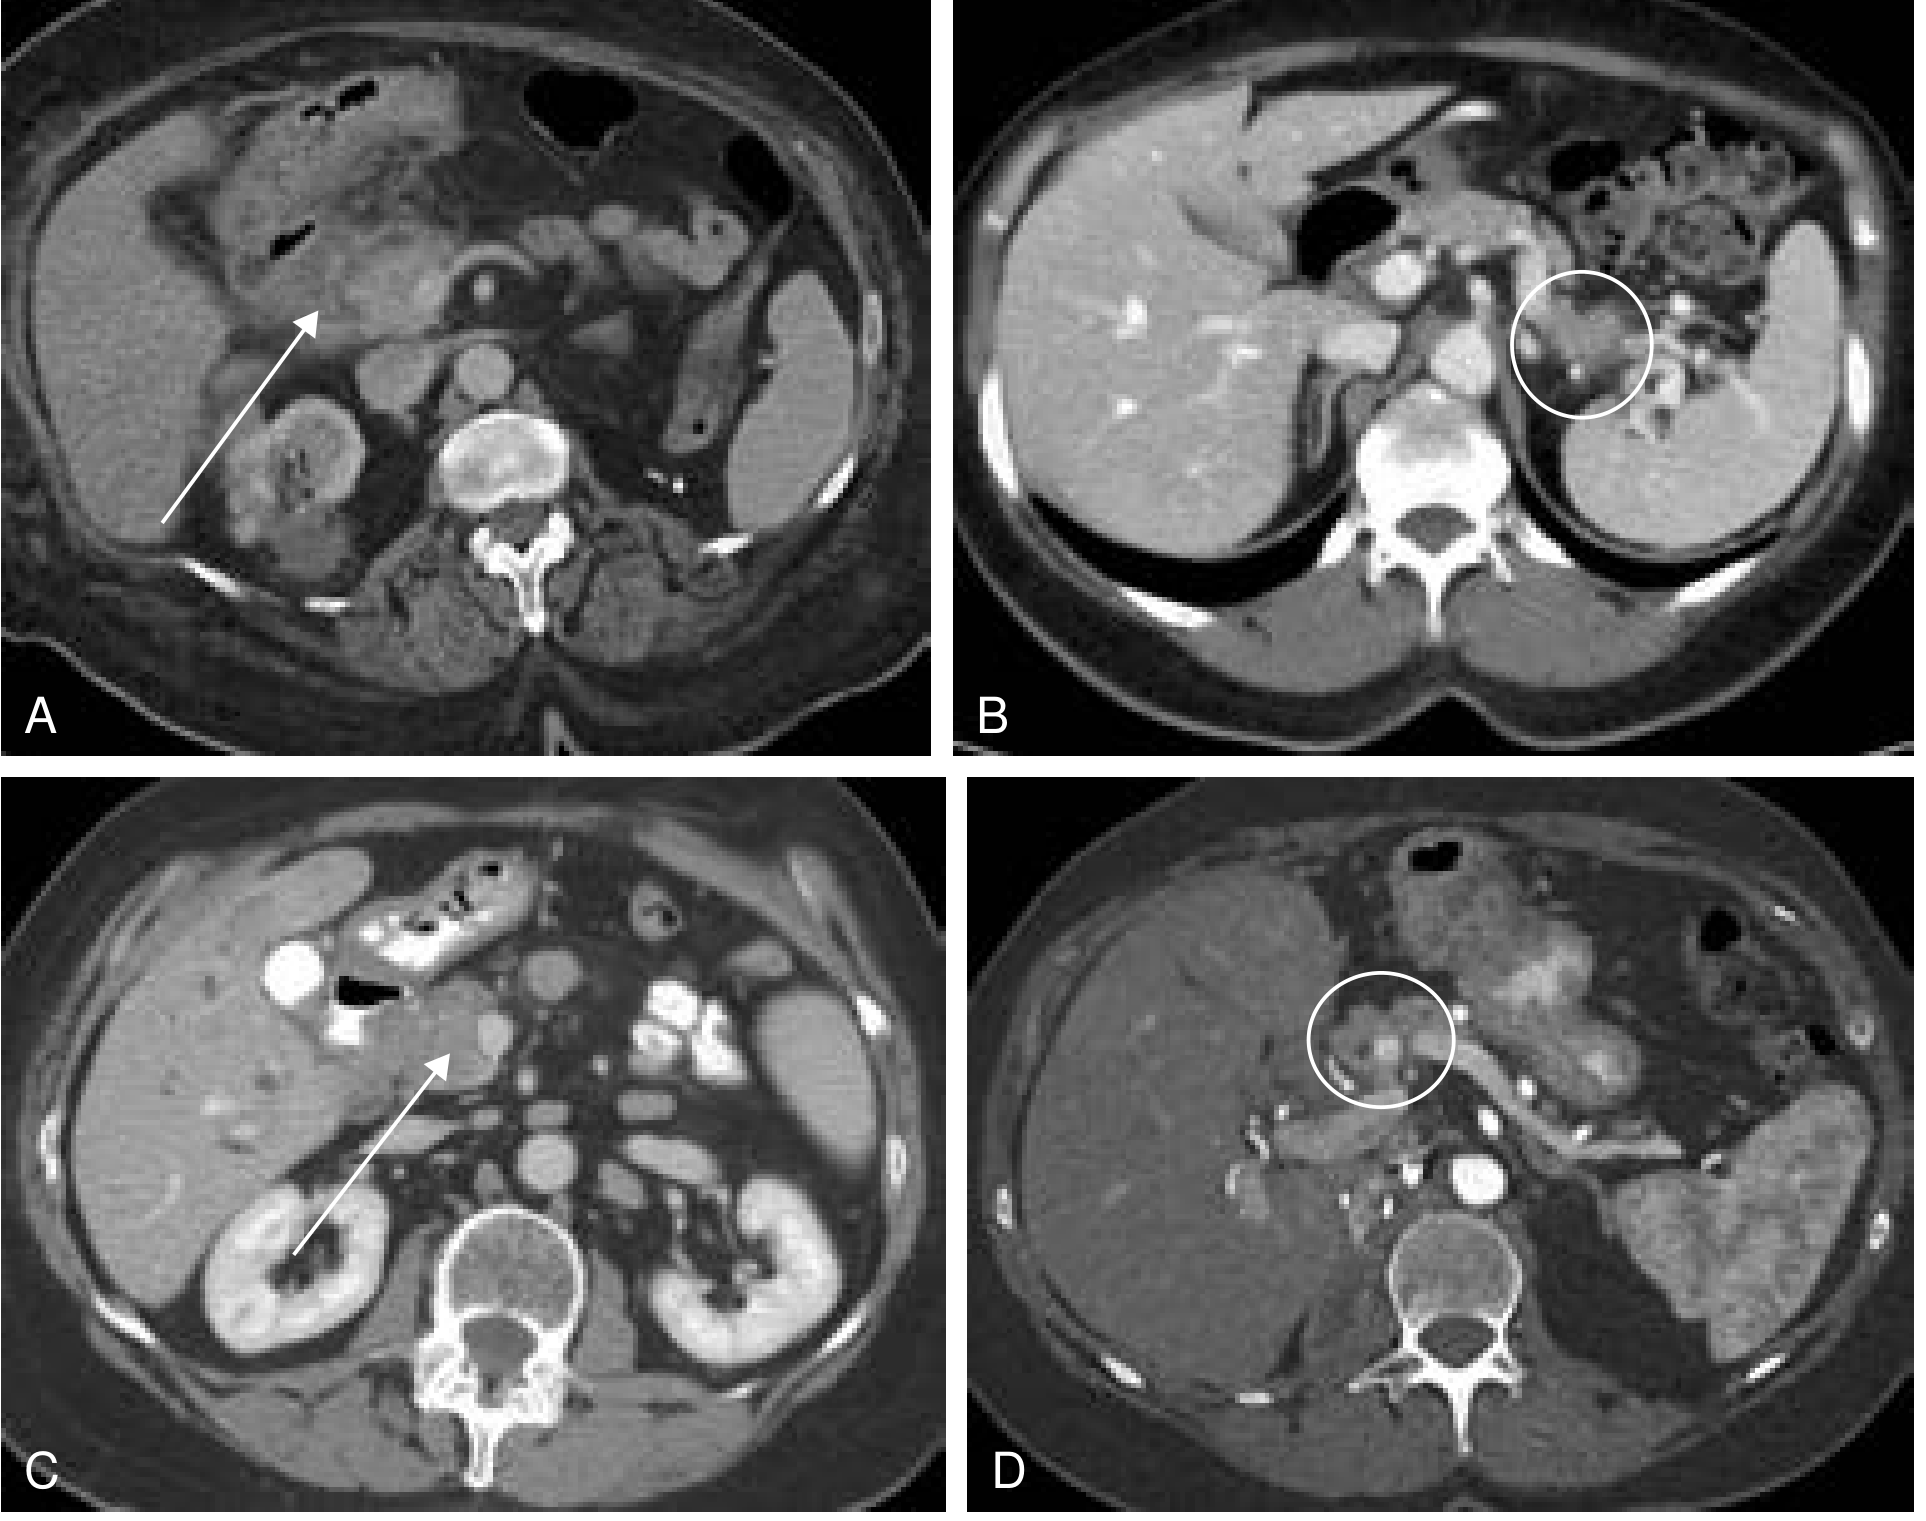

Fig. 8A (Current Surgical Therapy 14e) — CT showing groove pancreatitis with diffuse inflammatory stranding around the duodenal head and a 2.9-cm hypodense fluid collection (arrow):

CT showing groove pancreatitis with fluid collection and inflammatory stranding

Fig. 8 (Current Surgical Therapy 14e) — (A) shows groove pancreatitis with diffuse stranding/inflammatory changes around the duodenum and pancreatic head, with a 2.9-cm hypodense fluid collection (arrow):

CT showing groove pancreatitis with inflammatory changes and fluid collection

• Groove-predominant form: plate-like, hypoattenuating (low-density), poorly enhancing lesion situated between the pancreatic head and the descending duodenum (labeled "D" in the CT below — arrows point to the mass)

• Diffuse stranding and inflammatory changes surrounding the first portion of duodenum

• A curvilinear or cystic fluid collection in the groove — subtle but classic for groove pancreatitis

• Pancreatic and/or bile duct dilatation may be present

• The main pancreatic parenchyma is largely unaffected (groove-predominant form)

• Segmental form: the low-density mass extends into and involves the pancreatic head — difficult to distinguish from carcinoma